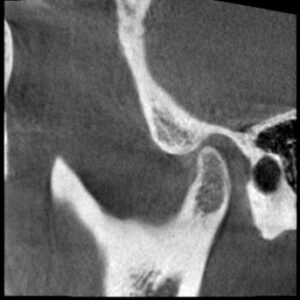

この状態のこの方の顎の関節のCTスキャンです。

左側の関節です。

関節の隙間が少なく、関節を圧迫していますから

つまり先にお見せした

動画と同じ状態ということです。

口が開くときも閉まるときも軟骨が外れて音がする。

まさにこの状態ということです。